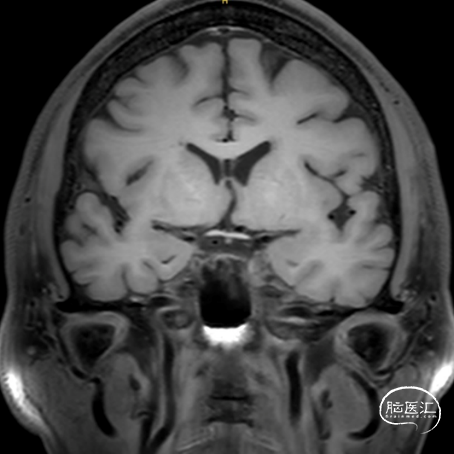

术前CT

男性,59岁。

主诉:诊断发现左侧A1段动脉瘤1年。

既往史:高血压、高血脂、高血糖。

1. 未破裂囊性动脉瘤

2. 起源于A1段背侧